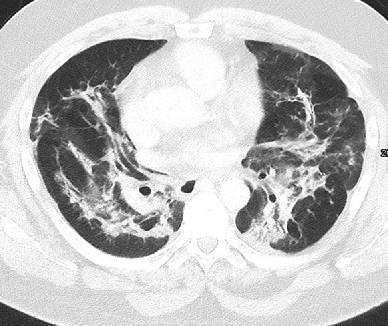

Whereas colitis is more common with ipililumab therapy, pneumonitis is more commonly seen with PD-1 inhibitors nivolumab and pembrolizumab [23]. According to a meta-analysis including 3232 patients treated with PD-1 inhibitors and 1806 patients with PD-L1 inhibitors (atezolizumab, durvalumab, and avelumab), it seems that PD-1 inhibitors have a higher incidence of pneumonitis compared with PD-L1 inhibitors [27]. According to Khunger et al., the incidence of pneumonitis treated with PD-1 inhibitors was 3.6% (95% CI 2.4–4.8%) as compared to 1.3% (0.8–1.9%) in patients treated with PD-L1 inhibitors. Pneumonitis can be a life-threating complication and therefore needs particular attention. According to the classification of the American Thoracic Society/European Respiratory Society for interstitial pneumonias, a recently published study of 20 patients with nivolumab-induced pneumonitis identified the following four CT patterns[28]: cryptogenic organizing pneumonia (COP) in 65% of patients (Fig. 2), non-specific interstitial pneumonia in 15% of patients, hypersensitivity pneumonia in 10%, and acute interstitial pneumonia (AIP)/acute respiratory distress syndrome (ARDS) in 10%. Radiologists should seek to differentiate pulmonary irAEs from other pulmonary pathologies such as bacterial pneumonias or radiation-induced toxicities. Individually this can be difficult, as the reaction patterns of the lung are limited and show a higher overlap between irAEs and non-irAE pathologies.

Fig. 2

Organizing pneumonia in a 53-year-old man with epithelial cell carcinoma showing patchy opacities in both lungs and sparing of the subpleural space